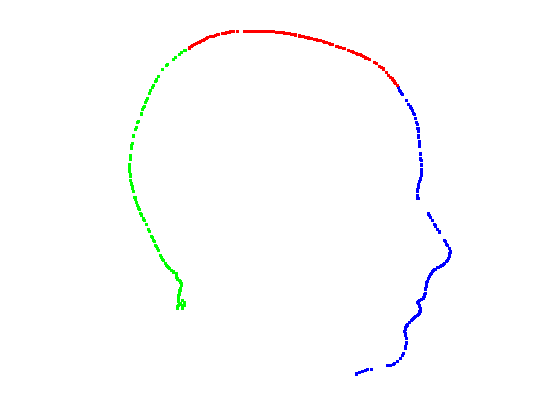

Given a set of points that lie on a symmetry plane, we divide the points into three groups by segmenting them at angles of 45 degrees and 135 degrees relative to the origin, as shown in Fig. 13. This gives us three profiles that we can model with spline functions.

|

|

|

|

For each of the three segments, we determine the range of gradients on that segment by simple differencing between consecutive points. Each segment is rotated into a 2D frame such that maximum absolute values of positive and negative gradients are equal. Cubic spline contours are fitted to the three profiles and the head profile contour is reconstructed using the three individual cubic splines. Fig. 14 show examples of these.